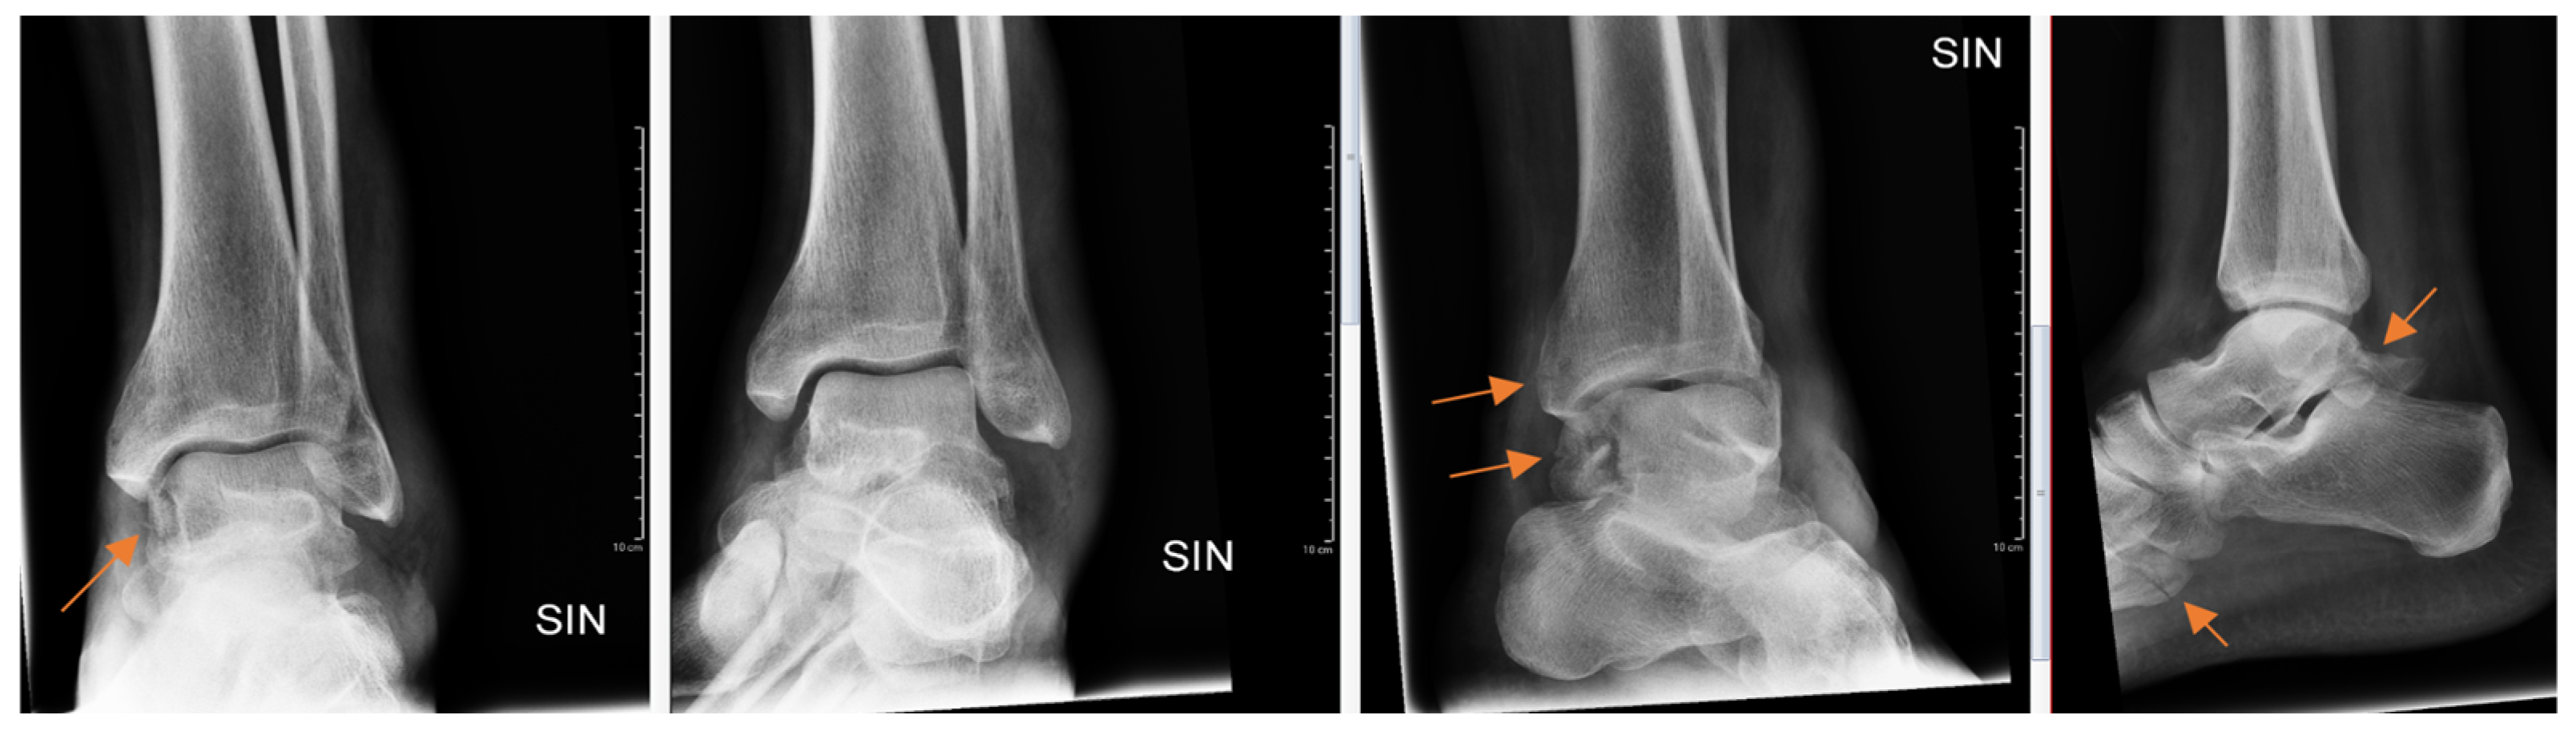

Radiology specialists interpreted more radiographs as having subtle findings compared to residents (p = 0.04). Different age groups did not differ (p = 0.89) between subtle or obvious cases. Radiology specialists missed correct diagnoses in subtle and obvious radiographs in 33% and 4.9%, respectively. In contrast, residents missed correct diagnoses in subtle (Figure 2) and obvious (Figure 3) radiographs in 51% and 8.4%, respectively.

Figure 3.

Patient with ankle trauma. Multiple obvious findings (arrows) in radiographs that were all missed by the resident.